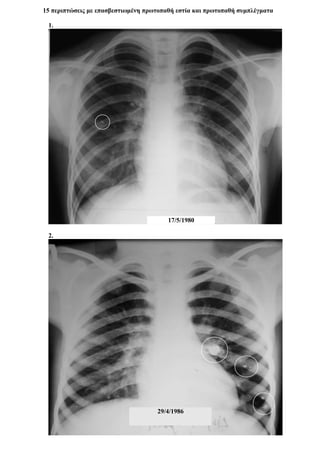

- Περιπτώσεις με επασβαστιωμένη πρωτοπαθή εστία και πρωτοπαθή συμπλέγματα 109

Περίπτωση 15η:

Α/Α Φ Η ΤΡΟΠΟΣ ΔΙΑΓΝΩΣΗΣ ΑΚΤΙΝΟΓΡΑΦΙΑ ΑΝΤΙΦΥΜΑΤΙΚΗ ΑΓΩΓΗ ΔΘ ΕΚΒΑΣΗ

15 Α 6

ΠΕΛ ΤΕ ΝΣ

+

+ ++ +++

R

ΙΝΗ

Μ

Z S Νοσ.

Σπ.12

ΙΑ

Ιν.Στ. Υπ.Βλ ΕΠ Θ.

15.α.

15.β.

28/5/1992

15.γ.

15.δ.

15.ε.